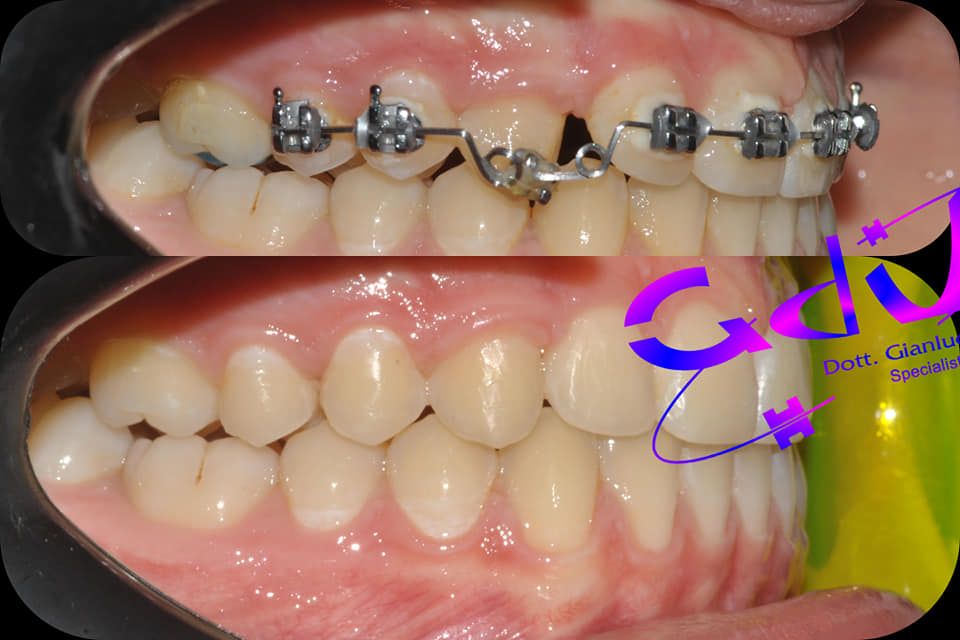

Il dottor Gianluca del Vecchio si occupa esclusivamente di ortognatodonzia, grazie anche alla collaborazione multidisciplinare di una équipe davvero entusiasmante e all’utilizzo di strumenti diagnostici e terapeutici all’avanguardia in ortognatodonzia. Particolare è la sua capacità di condurre i giovani pazienti ad affrontare, nella massima sicurezza emotiva e clinica, qualsiasi eventuale condizione di dolore derivante, ad esempio, da carie o da altre patologie, ma soprattutto di risolvere tutte quelle condizioni di “denti storti”, così spesso causa di disagio psicologico o di fenomeni deprecabili, quale il bullismo.

Queste le ragioni che consentono di trattare le malocclusioni, sia dei bambini che degli adulti, con protocolli scientificamente validati come i più veloci, affidabili e confortevoli.

Il dottore ha acquisito una concezione quanto più pratica e moderna della disciplina e utilizza apparecchietti di diversi colori di tipo mobile e fisso, ma anche terapie sia estetiche che invisibili, fiore all’occhiello di poche realtà in Italia. Per terapie estetiche e invisibili si intendono quelle in grado di spostare i denti, senza che traspaia nulla dalla bocca o con stelline e fili bianchi, esattamente come i denti del paziente.

Ma ancora di più l’équipe è in grado di offrire un servizio davvero unico: la tecnica dei retainer attivi. Questa consiste in fili o bottoni che si incollano dietro i denti e che, quindi, nascondono completamente la terapia. Questo tipo di prestazioni aiuta a superare la grande difficoltà psicologica, che spesso si insinua anche negli adulti, di dover spostare i propri denti per un sorriso perfetto: si consideri che tale difficoltà non viene affrontata, il più delle volte, proprio per l’imbarazzo che una apparecchiatura ortodontica genera in chi la usa. Queste tecniche, insieme alle mascherine invisalign invisibili di cui è provider ufficiale e agli attacchi in ceramica, sono tutte quotidianamente utilizzate presso i nostri reparti, in cui è possibile associarle in un discorso multidisciplinare a tutte le altre esigenze della odontoiatria classica.